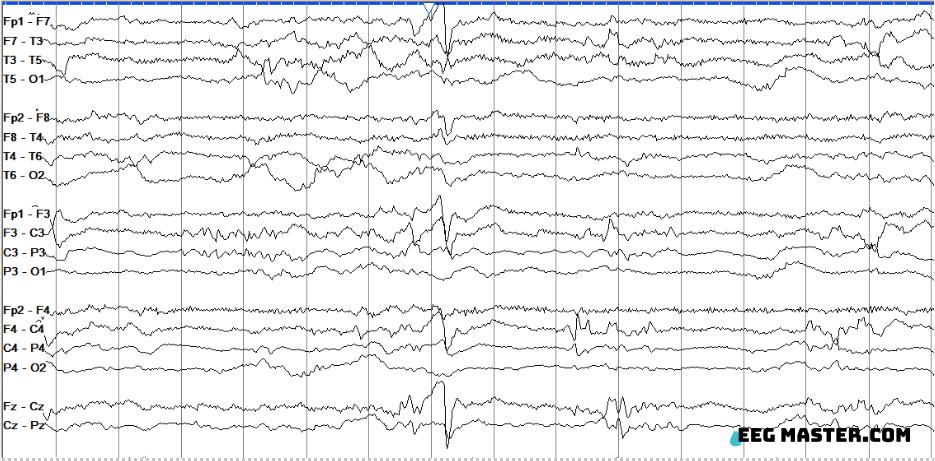

The following EEG is from a patient in the ICU. Based on the ACNS standardized critical care EEG terminology from 2021, what best describes the EEG finding. Click on this link to view the options, submit your answer and see the explanation. eegmaster.com/eegmaster/quiz….